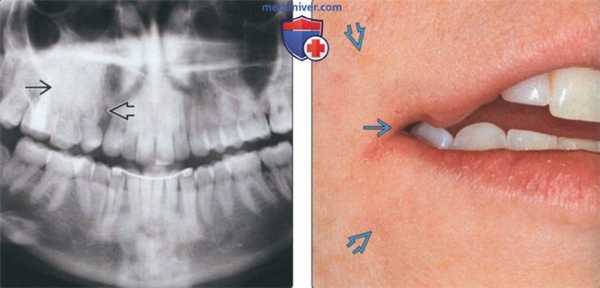

(Слева) На кадрированной панорамной рентгенограмме у женщины 26 лет определяется повышение плотности альвеолярной кости в области премоляров верхней челюсти справа. Визуализируется просветление между первым моляром и клыком, подозрительное на расщелину. О наличии расщелин сообщалось и в других случаях заболевания. Оба премоляра отсутствуют.

(Справа) На фотографии у этой же пациентки видна расщелина угла рта на фоне гиперпигментации лица. Эти нарушения часто сочетаются с СВО. Также наблюдается гипертрихоз.